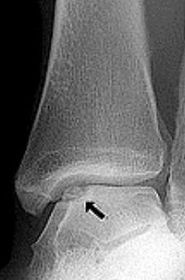

What is this? | Os subtibiale |

What disease is this? What does the arrow indicate? | Rheumatoid arthritis. Arrow = Bone erosion secondary to inflammation of retrocalcaneal bursa. |